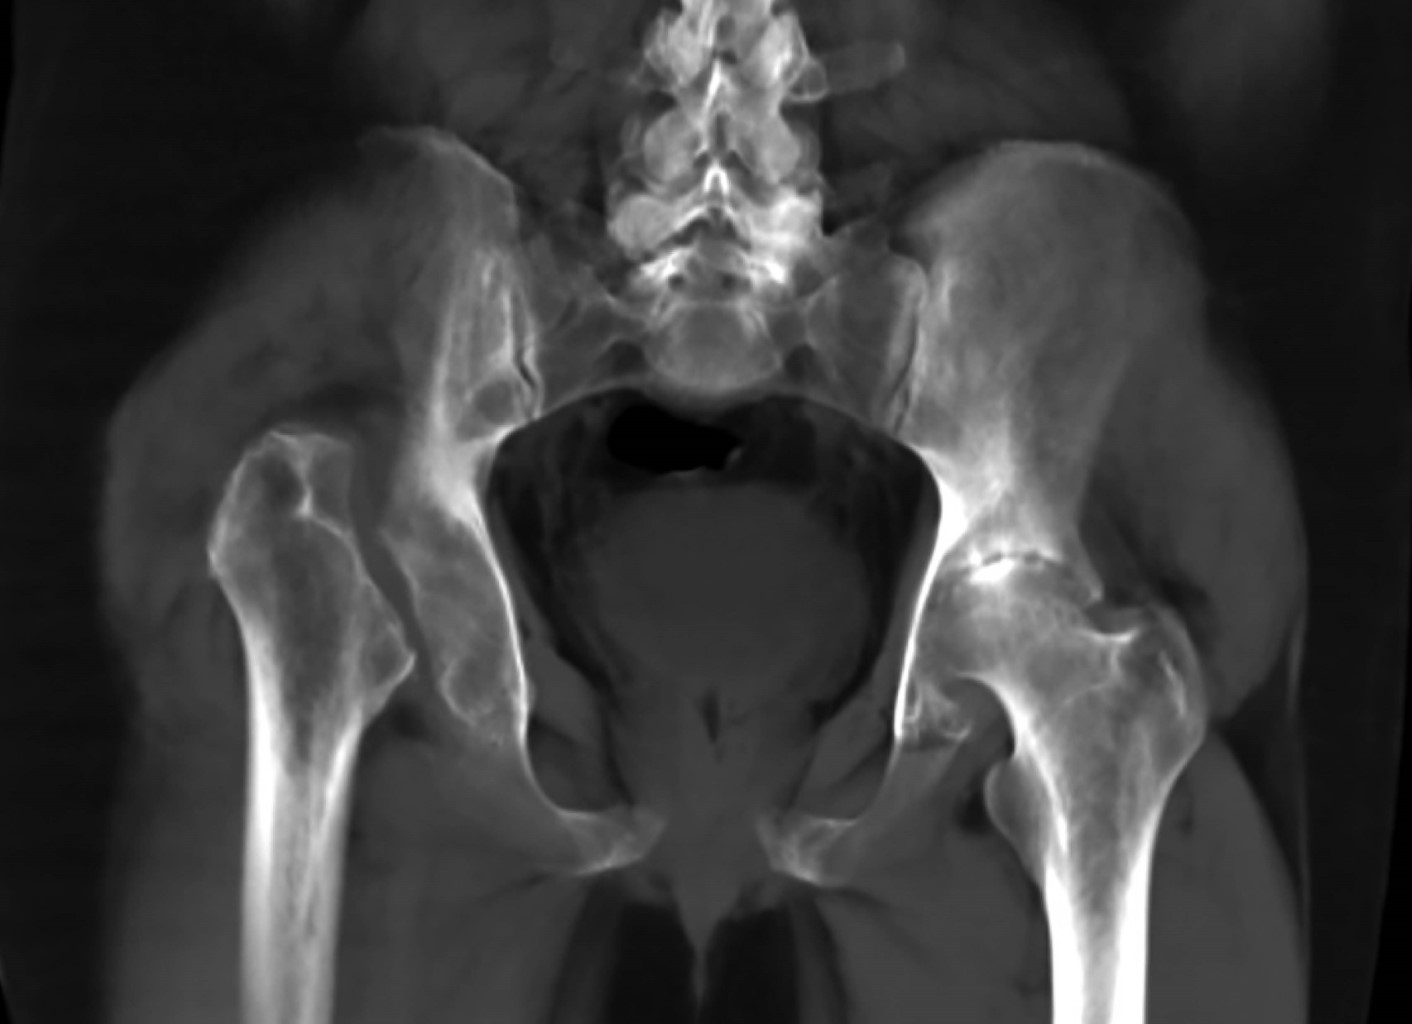

Introduction: Gorham-Stout disease is uncommon, characterized by the proliferation of endothelium-lined vessels and progressive bone destruction with spontaneous and progressive resorption. Case report: 39-year-old male with the evolution of pain in both coxofemoral joints, which increased over two years, presenting shortening of the right pelvic extremity, making ambulation impossible. The hip tomography showed disappearance of the right femoral head and neck and elevation of the greater trochanter due to dislocation, severe coxarthrosis was found in the left hip. Gorham-Stout syndrome was diagnosed and confirmed by biopsy.

Figure 1